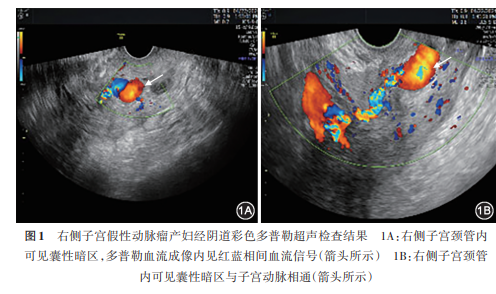

产妇于本次就诊3 h前突发下腹痛后大量阴道流血,色鲜红,多于月经量。体格检查:心率118次/min,血压102/80 mmHg,腹平软,无压痛及反跳痛,宫底脐耻之间,质硬,无压痛。产科检查:阴道内见少量暗红色血液,子宫颈光,外口松,子宫前位,增大如孕3月余大小,无压痛;双侧附件无异常。拟诊“晚期产后出血,子宫复旧不良”收入院。行急诊超声检查(经腹)提示:子宫颈管内混合回声结构(积血可能)。入院后查肝肾功能正常,人绒毛膜促性腺激素(β-human chorionic gonadotropin,β-hCG)5.6 U/L,血红蛋白水平99 g/L;予缩宫、止血、抗炎治疗,产妇出血量变少,病情稳定;2024年4月22日17:00又一次突发阴道大量流血,出血量约1 280 ml;休克指数(shock index,SI;为心率与收缩压的比值)为1.56;立即予输血、抗休克治疗,同时行经阴道彩色多普勒超声检查提示:右侧子宫颈管内见2.0 cm×1.7 cm的液性暗区,边界清,多普勒血流成像内见红蓝相间血流信号,右侧子宫动脉与该囊性暗区见分流口( 图1 )。超声诊断:偏右侧子宫颈管内囊性暗区[子宫假性动脉瘤(uterine artery pseudoaneurysms,UAP)可能],予麦角新碱0.2 mg缩宫治疗,并予阴道前后穹隆填塞纱布后出血稍缓解;同时行急诊盆腔血管造影,提示右侧子宫动脉末梢见类圆形造影剂外溢( 图2A ),诊断为右侧UAP,予明胶海绵颗粒及带纤维铂金弹簧圈栓塞,栓塞后造影复查假性动脉瘤征象消失( 图2B );左侧子宫动脉造影未见造影剂外溢,予明胶海绵栓塞后造影,与瘤腔无交通( 图2C )。手术疗效显著,产妇术后无阴道流血;术后3 d复查彩色多普勒超声示:假性动脉瘤瘤腔消失;恢复良好,于动脉栓塞后4 d出院;目前随访中。

通常,UAP的诊断借助彩色多普勒超声及CT、磁共振成像(MRI)、数字减影血管造影(DSA)即可确诊,其中无创、经济的经阴道彩色多普勒超声检查是诊断本病的最常用方法。在超声二维灰阶图像上,假性动脉瘤表现为无回声囊,在彩色多普勒图像上显示红蓝相间的动脉湍流而形成的“阴阳征” [ 4 ] 。若临床医师未将UAP作为需排除或考虑的疾病,选择了经腹超声检查而不是经阴道彩色多普勒超声检查,则可能导致误诊。本例首次超声检查因急诊选择了常规经腹检查,回顾本例超声声像图,推测可能因超声科医师经验不足,未正确使用多普勒技术而误诊为“子宫颈管内积血”,治疗2 d后复查超声(经阴道)才得以明确诊断,改变了临床治疗方向。值得一提的是,与超声、CT、MRI检查相比,DSA依然是诊断和治疗UAP的“金标准”,其不仅具有决定性的诊断价值,还可直接指导栓塞治疗 [ 5 ]